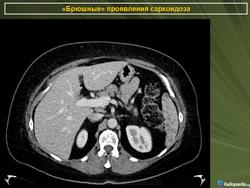

Саркоидоз селезенки и печени

Хотя саркоидоз печени и/или селезёнки обычно протекает бессимптомно, а увеличение уровня ферментов печени может быть небольшим, по данным исследователей из Японии методы визуализации (УЗИ брюшной полости, РКТ, ЯМР-томография и сканирование с галлием и технецием) могут легко выявить патологию. При лапароскопии можно видеть множественные узелки по поверхности печени или селезёнки, биопсия которых выявляет неказеифицированные эпителиоидные гранулёмы, содержащие многоядерные гигантские клетки, что особенно часто обнаруживают в области ворот органа (Kitamura M., Ishizaki T., 1994).

По мнению греческих рентгенологов очаговые изменения в селезёнке и печени являются необычными проявлениями абдоминального саркоидоза. Они описали случай саркоидоза, когда имелись множественные очаговые изменения пониженной плотности в печени и селезёнки на РКТ органов брюшной полости при нормальной рентгенограмме органов грудной клетки. Диагноз был подтверждён биопсией печени (Thanos L. et al., 2002).